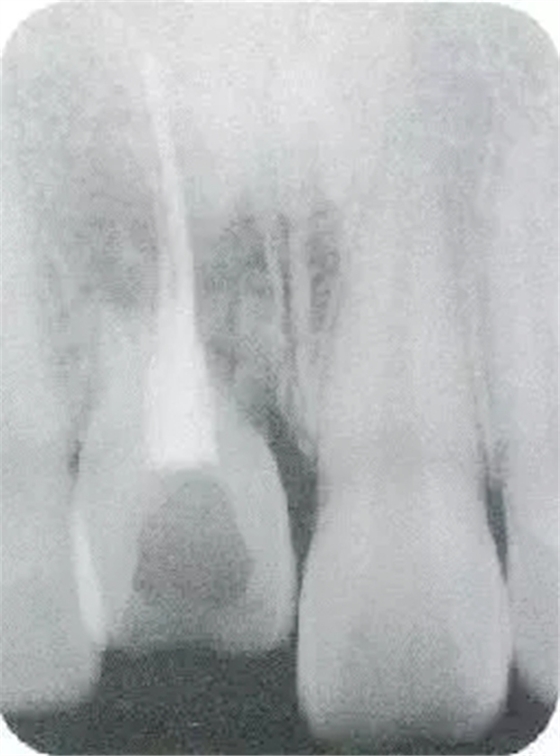

▲圖44-1,2

圖44-3

圖44-1~3 22歲,女性。交通事故3個月后來院。由于事故導(dǎo)致上頜右側(cè)前牙區(qū)凹陷且存在牙根吸收現(xiàn)象。圖片為初診時的前方照與根尖片。